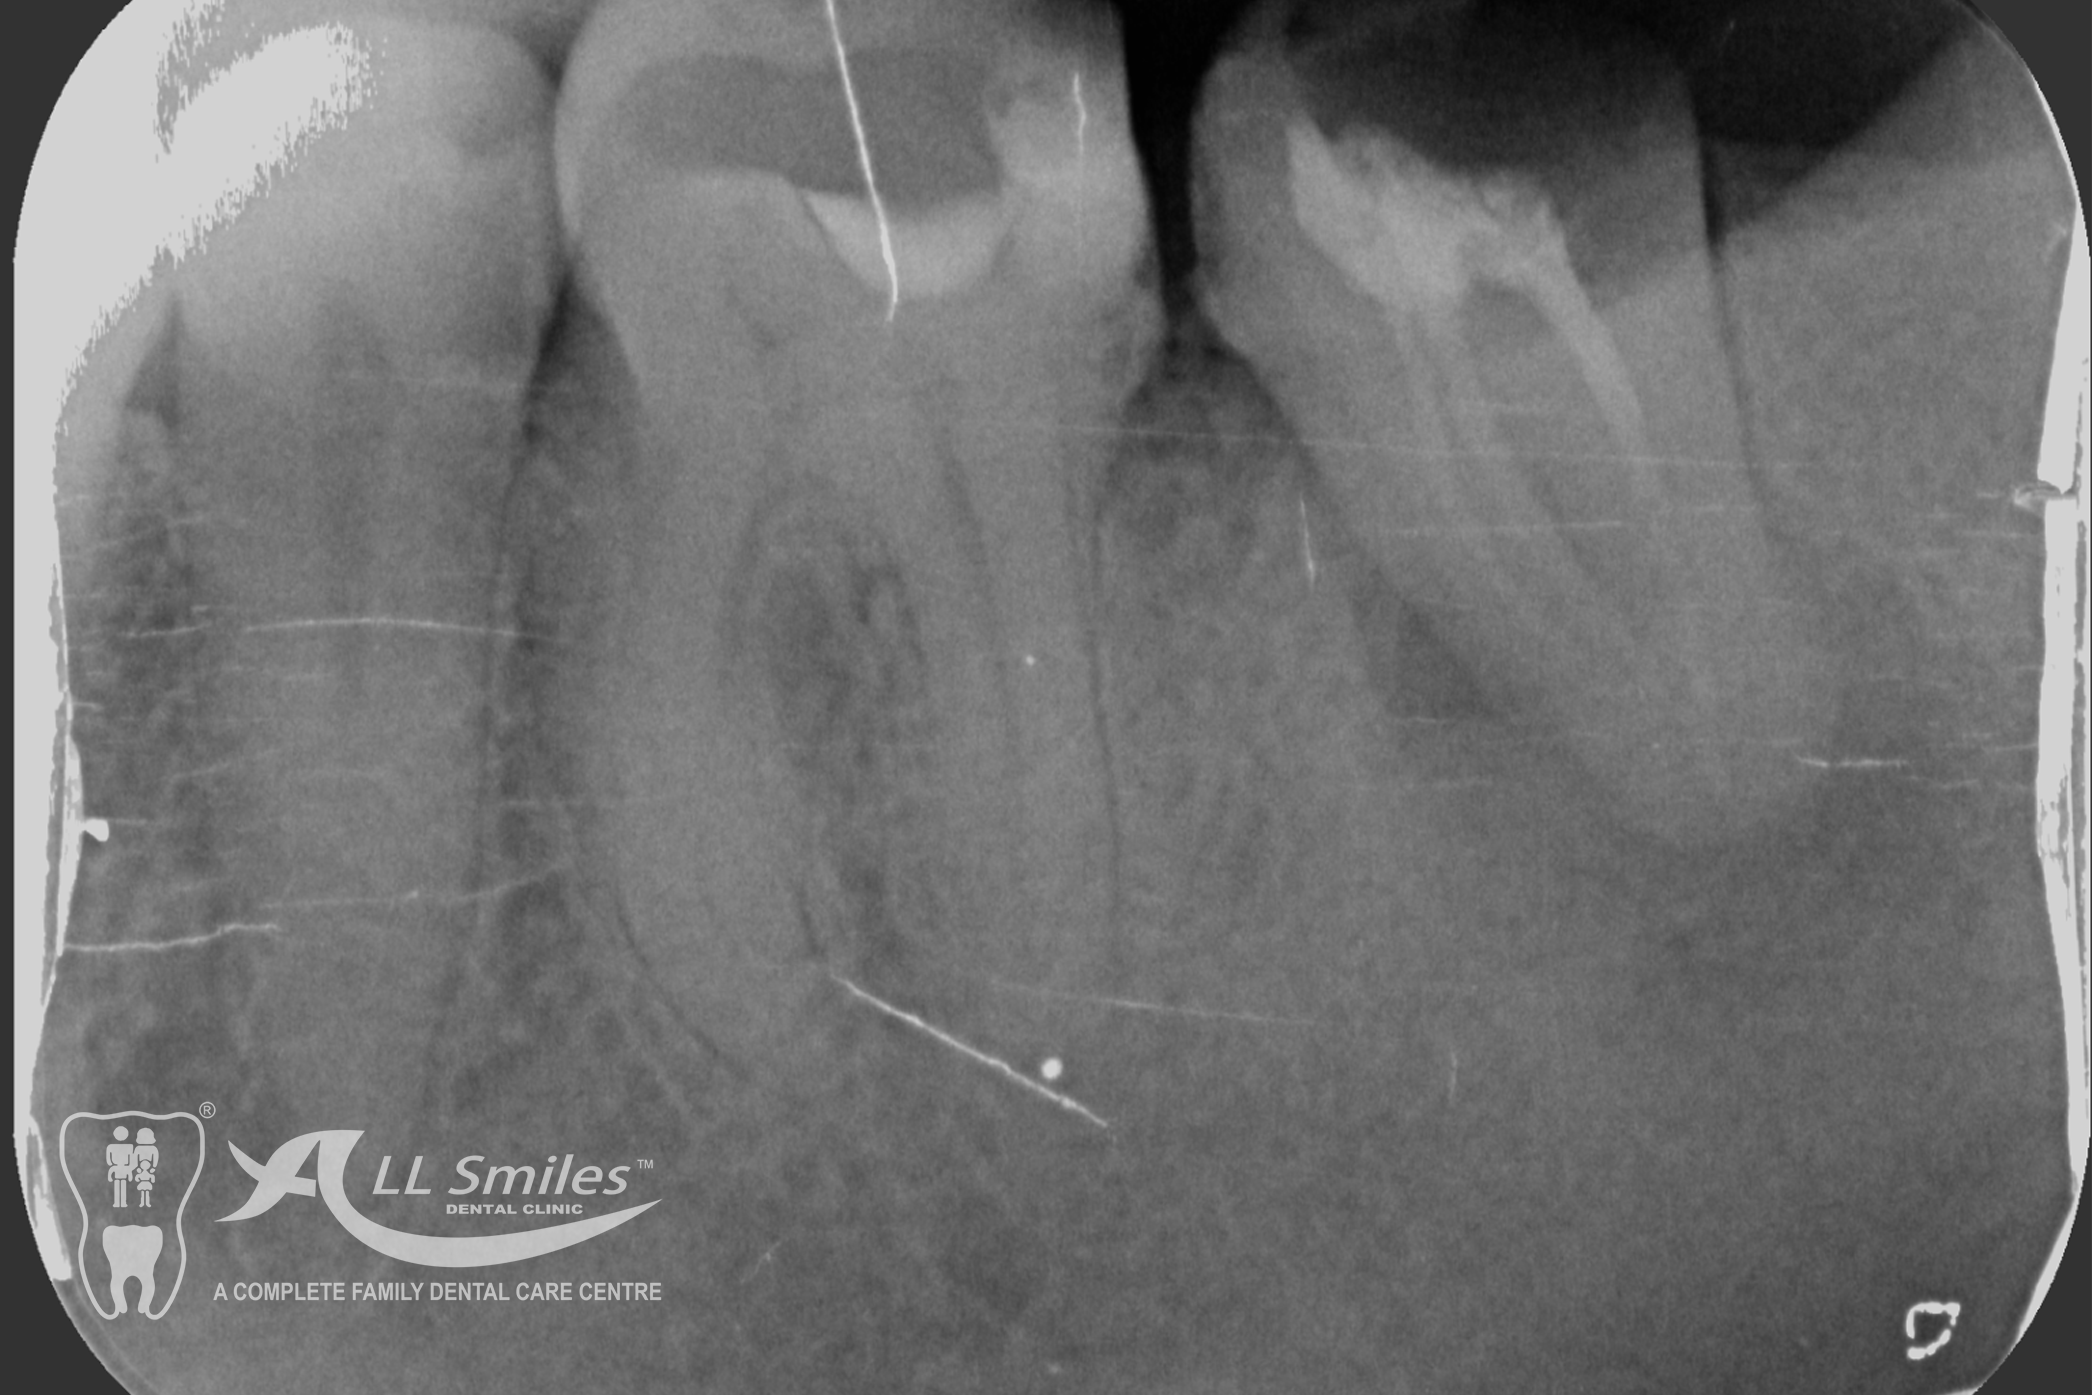

Root Canal Gallery